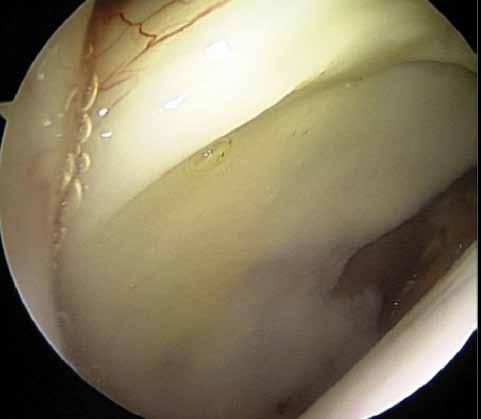

Fråga 2012-6 5p

Kvinna 57 årig tidigare frisk kvinna som inte tidigare har haft några problem med sina knäleder. En dag under vårens trädgårdsarbete känt smärtor i vänster knäled. Söker efter några dagar som jourfall då smärtorna snarast tenderar att öka. I status finner du lätt hydrops. Lätt rörelseinskränkning vänster jämfört med höger knäled. Lätt till måttlig ömhet medialt. Normal SR och CRP.

a. Differentialdiagnoser? (1p)

b. Hur handlägger Du patienten vid detta besök? (2p)

c. Hur utreder man ytterligare om patienten återkommer pga tilltagande besvär efter ett par veckor? (2p)

a. Troliga diagnoser är degenerativ meniskruptur/artros, spontan knäledsosteonekros eller insufficiensfraktur.

b. Noggrant knä- och höftstatus eventuellt slätröntgen och patientinformation om möjliga diagnoser. Smärtlindring och aktivitetsråd.

c. Vidare utredning med MR kan vara

indicerad speciellt för att kartlägga en eventuell osteonekros. Tc-scintigrafi kan också leda till rätt diagnos.